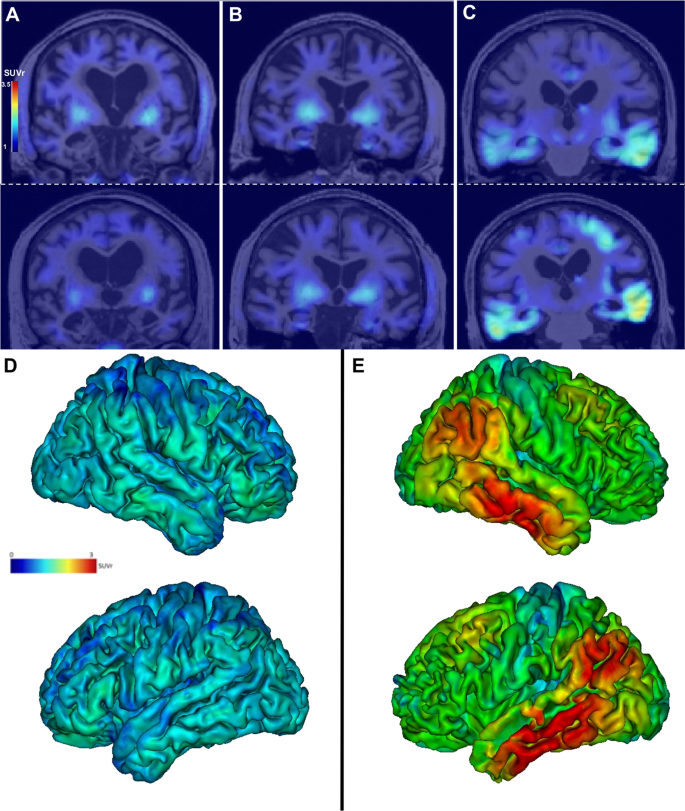

Individual PiB GCI and tau PET SUVr in all VOIs are detailed in Fig. 1.

Green boxes correspond to the lowest values and red boxes to the highest values. The boxes are framed when the SUVr is above the cut-off value defined from our control group. MMSE, Mini-mental State Examination; GCI, global cortical index; Parahippoc, parahippocampal gyri; Inf. Temp., Inferior temporal gyri; Mid.Temp., Middle temporal gyri; Post. Cing., posterior cingulate; Sup. Temp., Superior temporal gyri.

In AD patients, in addition to the positivity of PiB-PET, tau positivity extended beyond the medial temporal regions. In the SNAP group, PiB-PET was negative in 12/15 patients. The 3 SNAP patients with positive amyloid PET had negative tau PET, including no significant uptake in the entorhinal cortices, amygdala, parahippocampal or fusiform gyri. We found positive tau tracer binding restricted to the entorhinal cortices and/or amygdala in 5 (amyloid negative) SNAP patients (Figs. 1 and 2).

Individual tau PET SUVr images (coronal sections) in patient SNAP 5 A, in patient SNAP 6, who has increased tau radiopharmaceutical uptake in the entorhinal cortices and amygdala with negative amyloid PET (B), and in patient AD 9 (C) at baseline (top row) and after 2 years (bottom row). Note the off-target binding of the tracer in the basal ganglia in all patients. Projection of the mean cortical [18F]-Flortaucipir SUVr on the 3D MRI MNI template in the SNAP group D and the AD group E (mean images were obtained after normalisation of individual images to the MNI template). Lateral views of the right and left hemispheres are shown.